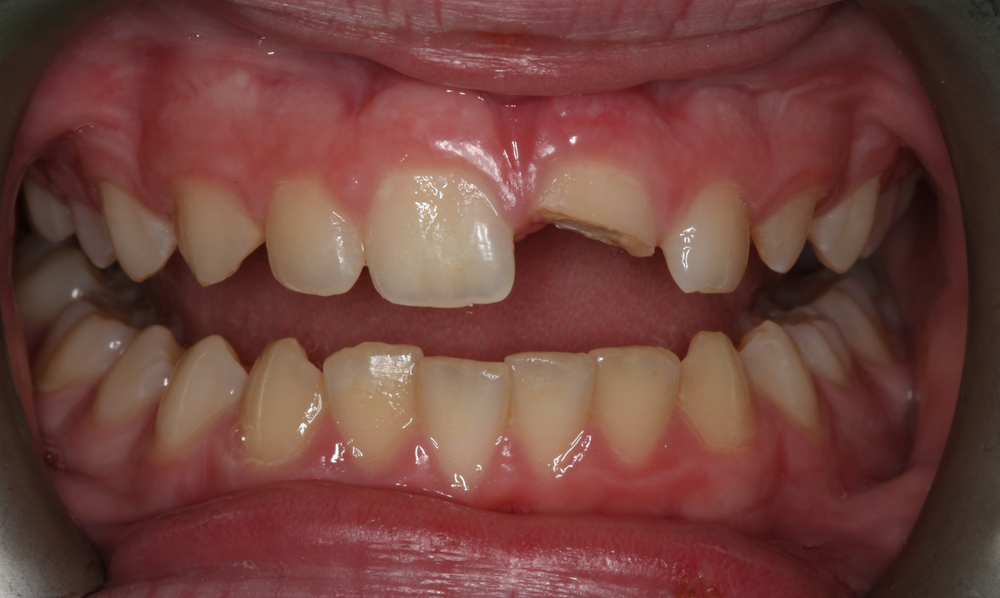

A 12-year-old male presented for a consultation for the restoration of the maxillary left central incisor (tooth No. 9), which was fractured when the patient was hit with a hockey stick while playing in gym class at school (Figs. 1 and 2). The patient had undergone endodontic treatment performed by an endodontist to stabilize the tooth one week earlier, and his parents were referred to the author via the American Academy of Cosmetic Dentistry (AACD) website.

Fig. 1 Fig. 2